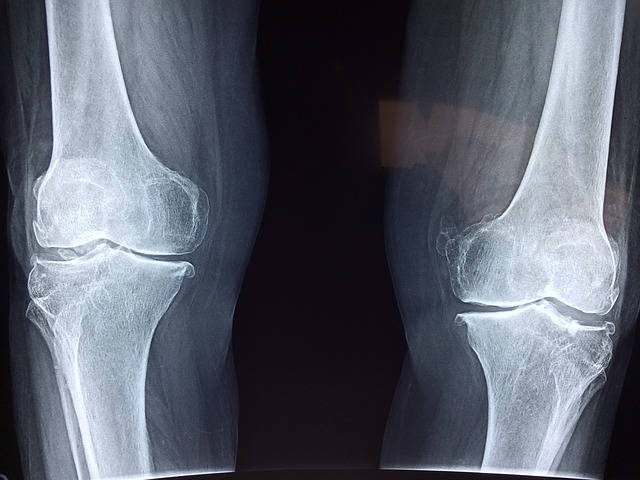

무릎 통증원인 - 퇴행성 관절염 퇴행성 관절염은 나이가 들면서 발생하는 관절의 퇴행성 변화로 인해 무릎 통증을 유발합니다. 연골이 닳아 없어지면서 뼈와 뼈가 서로 마찰되어 통증과 염증을 일으킵니다.